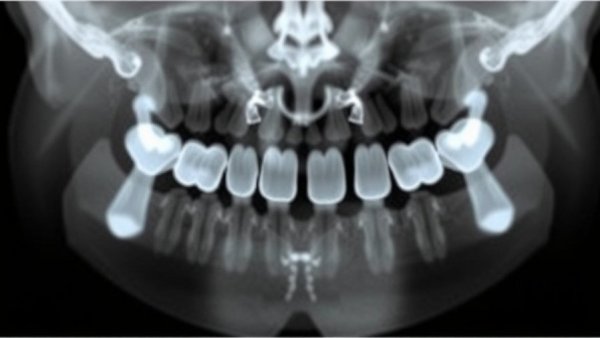

Dental implants are commonly chosen by many adults seeking to reclaim their smiles and enhance their quality of life. However, the long-term success of these implants is significantly influenced by the phenomenon known as marginal bone loss (MBL). Recent studies have shown that early radiographic bone loss, particularly within the first six months post-loading, offers crucial insights into the potential efficacy and longevity of dental implants.

Marginal bone loss refers to the gradual losing of bone surrounding dental implants, which can lead to serious complications such as implant failure or the need for additional surgeries. As reported in the literature, including key studies, MBL can be classified into two categories: high bone loser (HBL) and low bone loser (LBL). A notable threshold for concern has been identified—implants losing more than 0.5 mm of bone within the first six months after loading are deemed at risk of failure.

Detecting marginal bone loss early—especially before the 6-month mark—enables dentists and oral health professionals to intervene proactively. This early intervention can mitigate progressive loss and maintain the structural integrity and aesthetic function of the implant. In cases where the MBL remains below the recommended threshold, the implant is likely to be radiographically successful in the long run, reaffirming the importance of regular follow-up appointments and appropriate imaging, as emphasized in ongoing research.